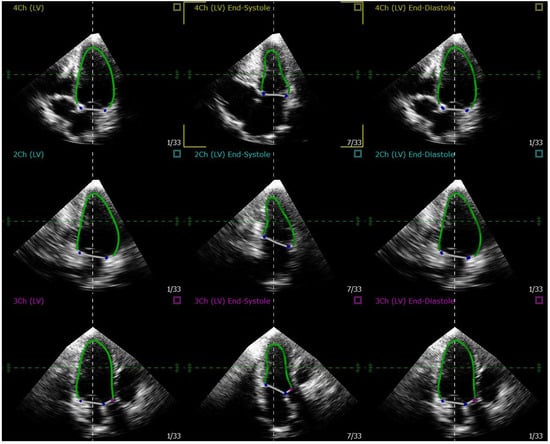

Cardiac Deformation Patterns During Exercise in Healthy Children

by Dario Collia, Ling Li, Mary Craft, Christopher C. Erickson, Zahi A. Fayad, Maria G. Trivieri, Jason Christensen and Gianni Pedrizzetti

J. Cardiovasc. Dev. Dis. 2025, 12(12), 488; https://doi.org/10.3390/jcdd12120488 - 10 Dec 2025

In the cardiovascular system, geometric remodeling of the cardiac chambers is the main mechanism enabling increased cardiac performance during exercise in athletes, as well as underlying pathological progression toward heart failure. In this study, we investigated cardiac mechanics in healthy children across five [...] Read more.

In the cardiovascular system, geometric remodeling of the cardiac chambers is the main mechanism enabling increased cardiac performance during exercise in athletes, as well as underlying pathological progression toward heart failure. In this study, we investigated cardiac mechanics in healthy children across five phases of physical exercise, Rest, Mid, Peak, and Recovery, at 5 and 10 min, using three-dimensional echocardiography. Analyses were conducted relative to a reference cohort of healthy children to identify exercise-induced modifications that may contribute to cardiac remodeling. Ventricular performance was assessed through two complementary approaches: myocardial deformation, quantified by the principal values and directions of the strain tensor, and intraventricular flow dynamics, including assessments of ventricular filling patterns as the vorticity, vortex formation time and hemodynamic forces. This preliminary study offers promising insights into early cardiac function changes that may inform our understanding of cardiac remodeling during adaptation, healing or disease progression. Full article